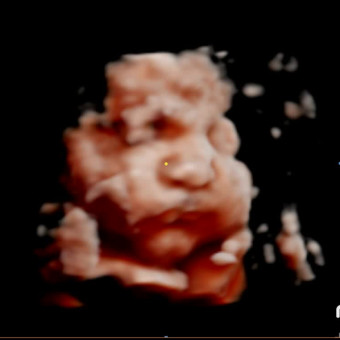

December 23, 2025

Waiting for our baby boy Rafael! Whatever you would like to help us in we would greatly appreciate it! Feel free to get something off the list or anything you find similar! Thank you all for the help and love we have received!❤️ No pressure, this list is also just for us to keep track of what we need for baby’s arrival💙